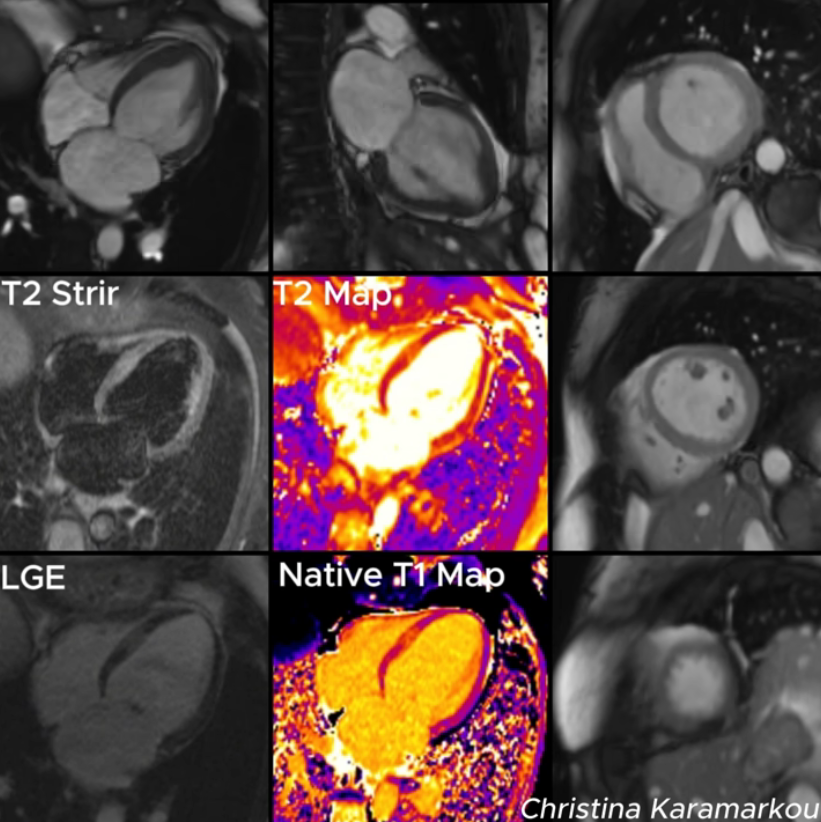

【影像学检查:心脏磁共振 CMR】 为进一步明确诊断,患者进行了 CMR 检查(见附带视频/动图)。 结果证实: 左室基底部和中段功能减退(运动减弱/消失),心尖部收缩功能保留。T2 序列显示基底部心肌明显水肿;病变节段的 Native T1 和 T2 值显著升高,但几乎没有明显的基底部心肌晚期钆强化(LGE)。 (注:CMR 在此非常关键,它显示了心肌水肿且只有极少的纤维化,帮助排除了心肌炎或心梗。)

至此,影像学特征符合基底部 Takotsubo 综合征(Basal TTS)。